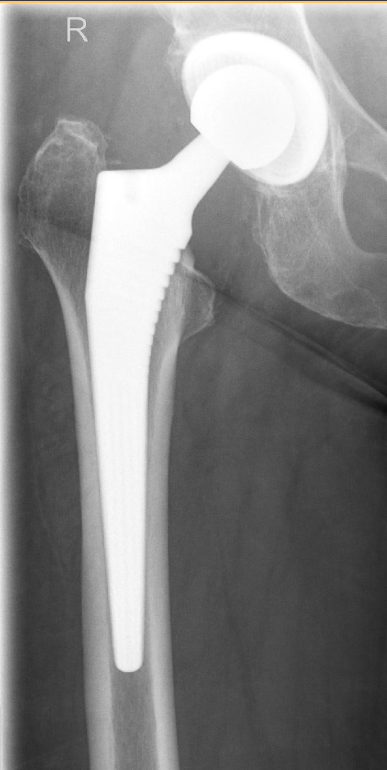

Künstliches Hüftgelenk – Hüftendoprothese

Bei der Hüfttotalendoprothese wird ein kaputtes Hüftgelenk vollständig durch ein künstliches Gelenk ersetzt. Dabei werden sowohl der „Kugelkopf“ des Oberschenkels als auch die „Pfanne“ im Becken durch künstliche Teile ausgetauscht, damit sich Betroffene wieder schmerzfrei und besser bewegen können.

Für die Diagnostik stehen moderne Verfahren zur Verfügung. In der Regel erfolgt zunächst eine Röntgenaufnahme, mit der das Ausmaß der Arthrose zuverlässig eingeschätzt werden kann. Ergänzend können MRT- oder CT-Untersuchungen sinnvoll sein, insbesondere bei unklaren Befunden oder zur OP-Planung.

Prothesentypen

Es stehen verschiedene Prothesentypen zur Verfügung, die je nach Alter, Knochenqualität und individueller Situation ausgewählt werden:

Zementfreie Prothesen

Wachsen fest im Knochen ein, besonders geeignet bei guter Knochenqualität

Zementierte Prothesen

Werden mit Knochenzement fixiert, bewährt insbesondere bei reduzierter Knochenqualität

Hybridprothesen: Kombination aus zementierter und zementfreier Verankerung

Es gibt Hybrid-Varianten, bei denen nur ein Teil zementiert wird, während der andere Teil zementfrei im ‚Pressfit‘-Verfahren verankert wird. Zum Beispiel kann die Pfanne im Pressfit-Verfahren und der Schaft zementiert werden, oder umgekehrt: der Schaft im Pressfit-Verfahren und die Pfanne zementiert.

Kurzschaftprothesen: gewebeschonende Variante, vor allem für jüngere Patientinnen und Patienten

Kurzschaftprothesen stellen eine knochensparende Variante dar, insbesondere für jüngere Patientinnen und Patienten mit guter Knochenqualität.